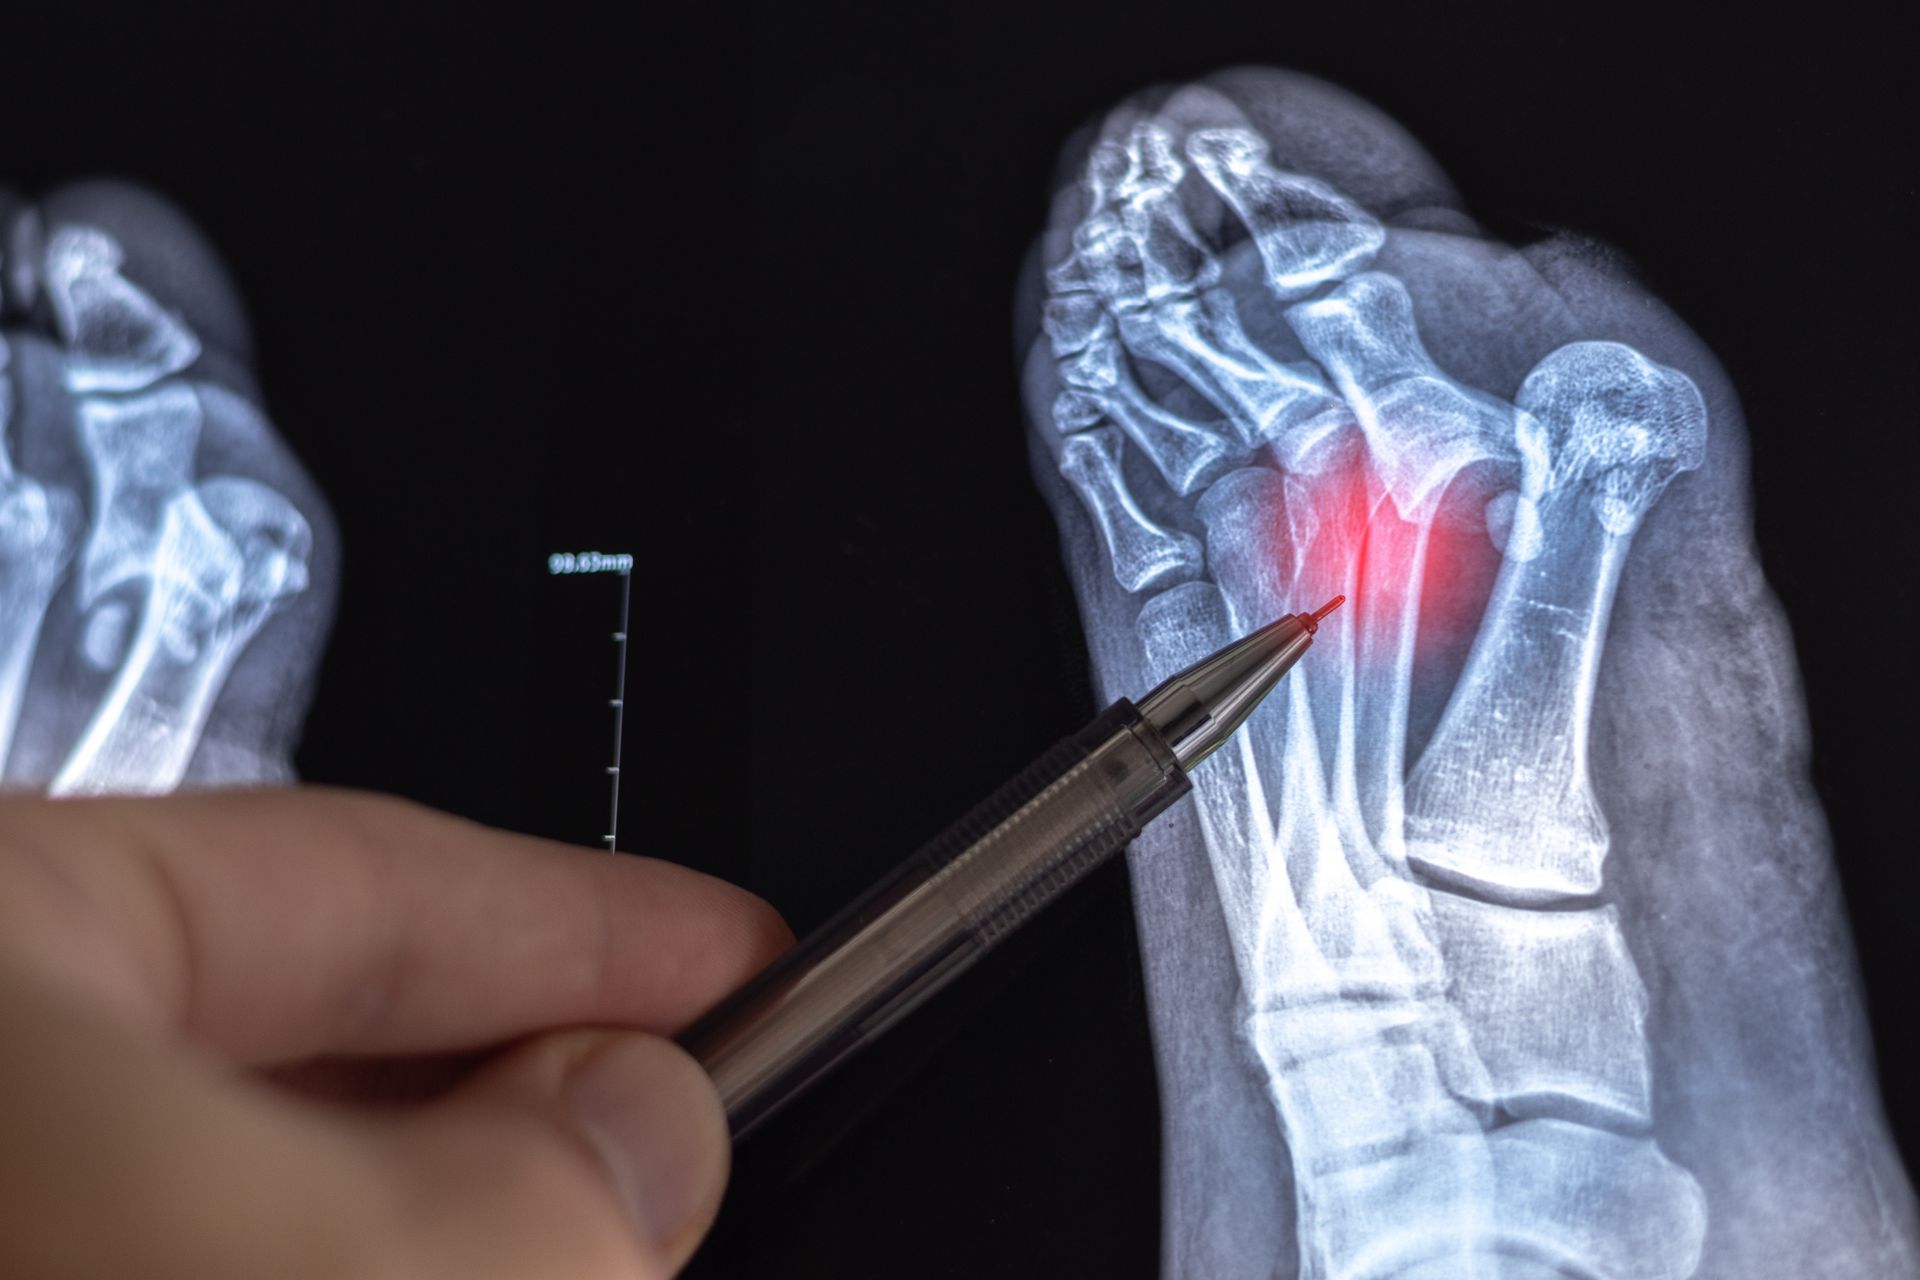

Foot and ankle fractures occur when one or more of the many bones in these complex structures crack or break, typically as a result of traumatic impact, twisting injuries, falls, or repetitive stress over time. These injuries can range from hairline stress fractures that develop gradually to severe displaced breaks that cause immediate and intense pain, swelling, bruising, and an inability to bear weight — all requiring prompt and accurate diagnosis to ensure proper healing and prevent long-term complications.

We utilize advanced imaging including X-rays and CT scans to precisely identify the location, type, and severity of your fracture and determine the most appropriate course of treatment. Depending on your injury, our approach may include immobilization with casting or bracing, surgical fixation using plates, screws, or pins to realign and stabilize the bone, and a structured rehabilitation program to restore strength and mobility as healing progresses.